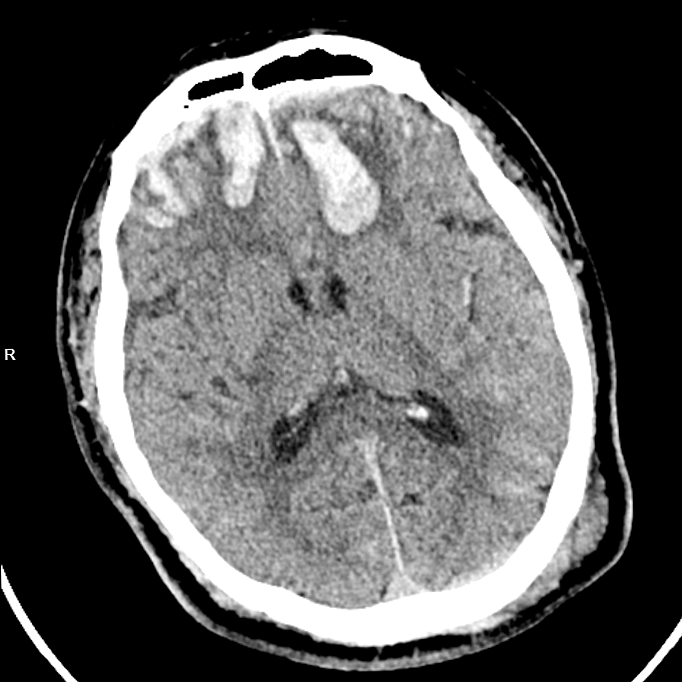

【严重脑挫裂伤】

胸外科医生率先出手,紧急置入胸腔闭式引流管,成功排出压迫肺部的血气胸,为呼吸功能争取喘息空间;神经外科团队紧盯颅内情况,精准用药控制脑挫裂伤引发的脑水肿,严防脑出血恶化;骨科团队则针对右侧肱骨骨折制定手术方案,为后续康复打下基础。